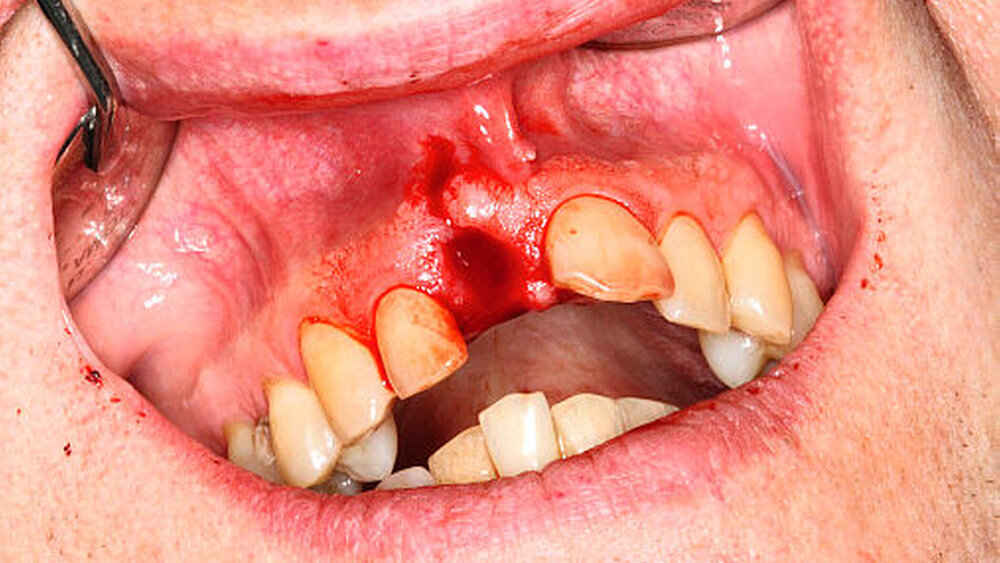

Die Avulsion bezeichnet die vollständige Verlagerung des Zahnes aus dem Alveolenfach (Abbildung 2). Schnelles und richtiges Handeln mit Einleitung der oben genannten Sofortmaßnahmen am Unfallort kann die Prognose des Zahnes erheblich verbessern [Andreasen JO, 1981a-b, Andreasen, 1995; Andreasen, 1995a-d; Barrett, 1997; Ebeleseder, 1998; Trope, 2002; Pohl, 2005a-c; Andreasen, 2007; Day, 2012].